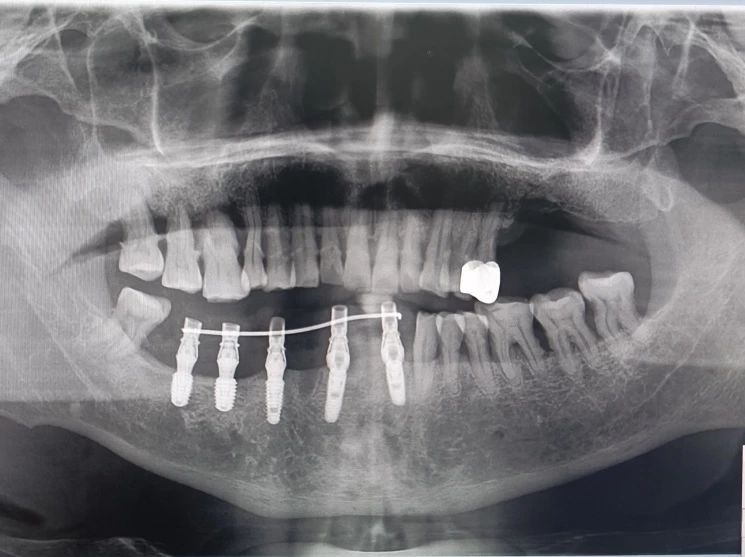

-下颌即刻种植+即刻修复后-

-下颌即刻种植+即刻修复后-